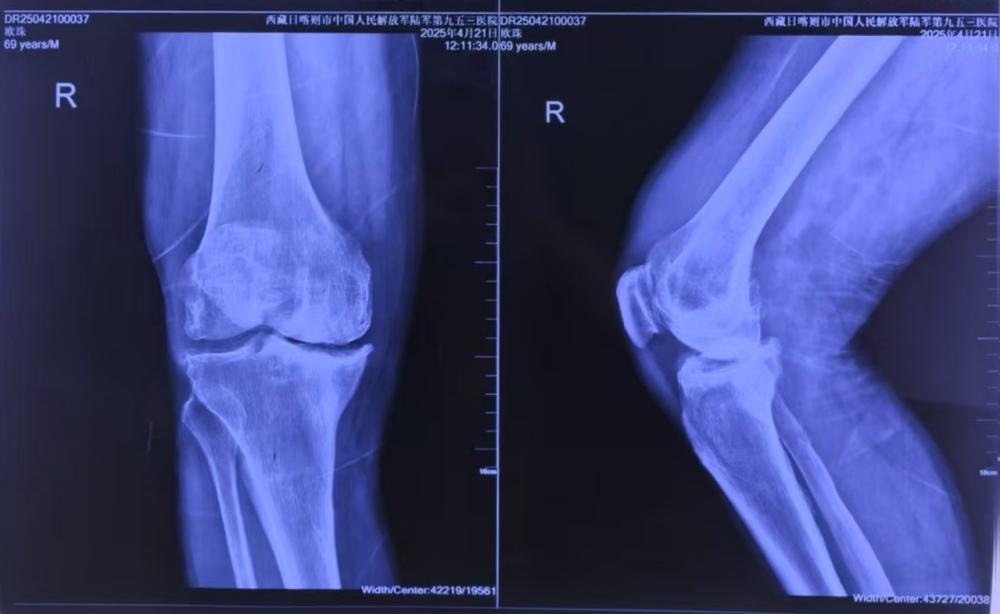

患者常年受双膝疼痛折磨,右膝严重内翻畸形伴骨缺损,步行百米即需歇息。传统手术面临三大“高原枷锁”:患者骨骼“塌方式”缺损,假体匹配难度倍增;医生需克服高原反应,设备需在低压低氧环境中稳定运行;生物膝严苛标准,截骨误差需小于1毫米,压力失衡将导致假体寿命骤降50%。

患者术前CT